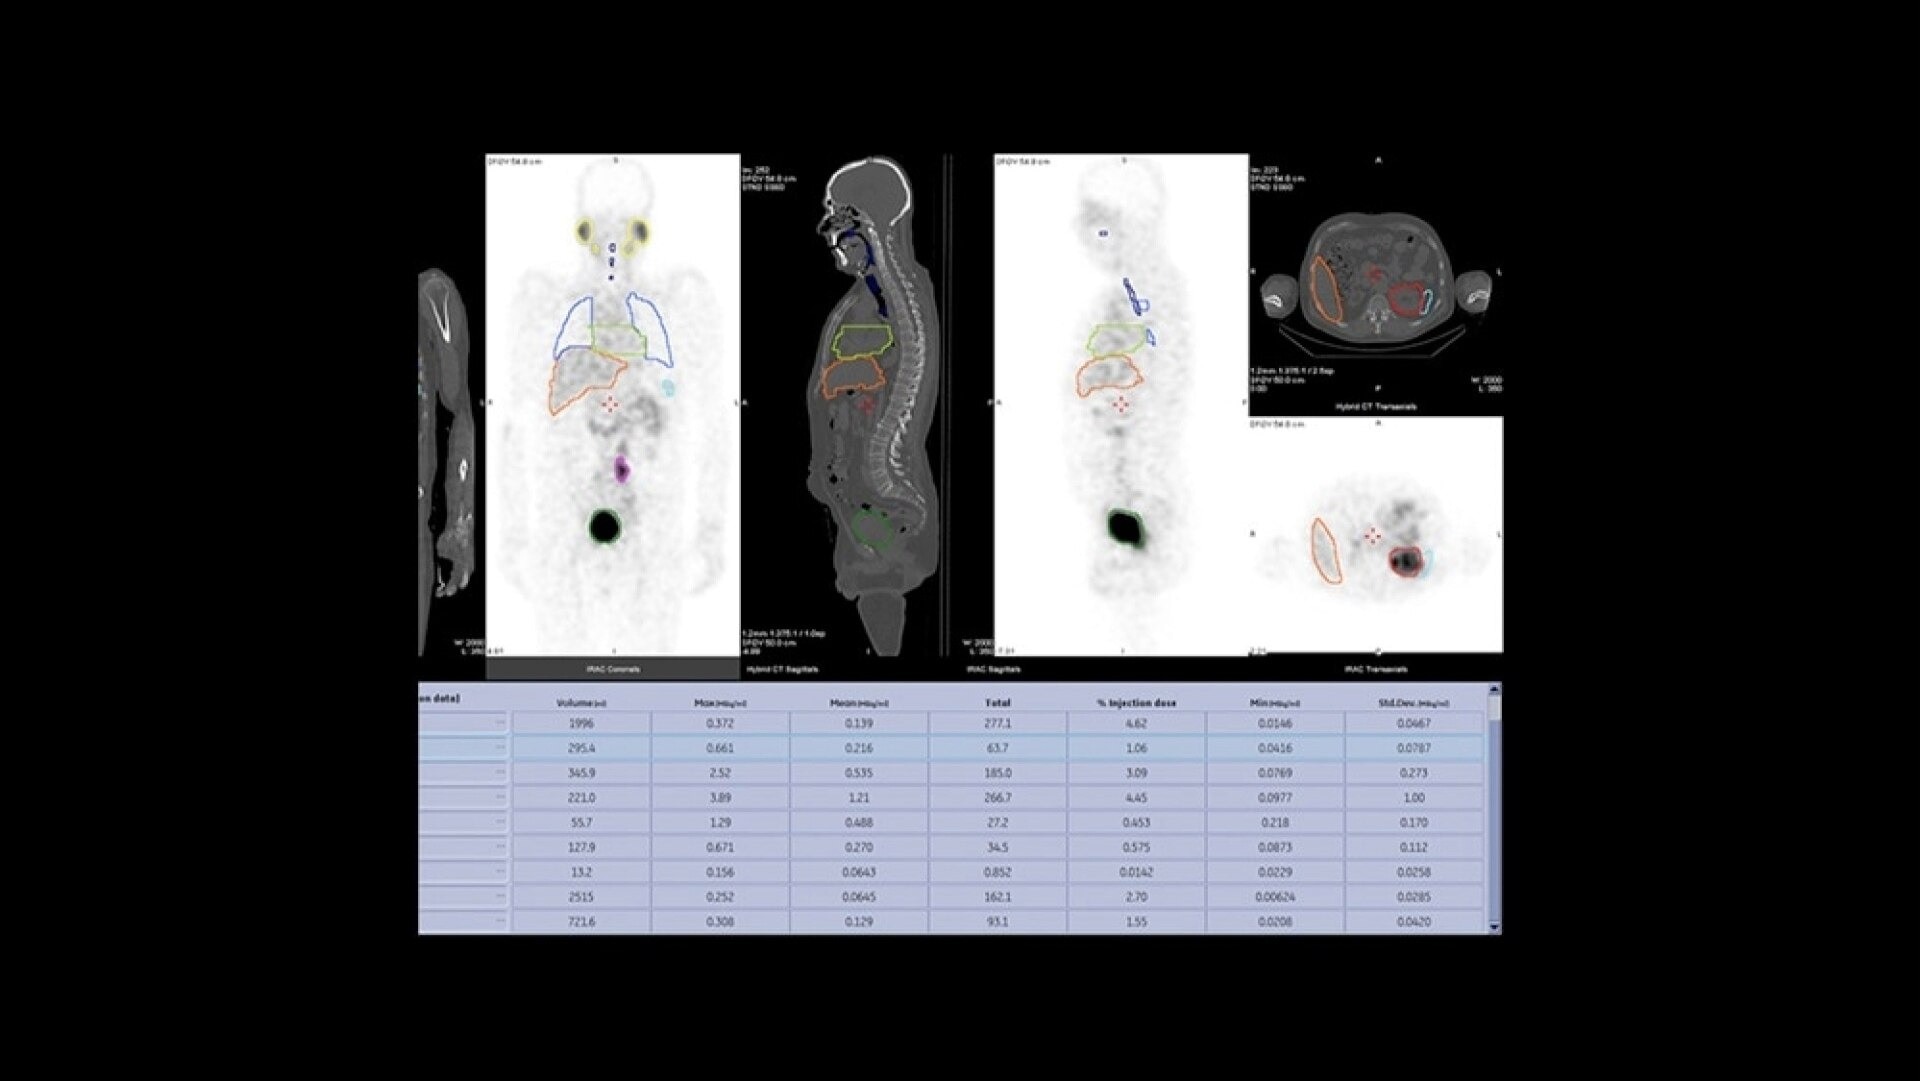

Quantitative SPECT/CT for every patient, every day

NM/CT 870 CZT is a SPECT/CT built for consistent, reproducible quantitation. Improvements to detector performance enable exceptional spatial and energy resolution. It also leverages CT-based attenuation and scatter correction along with Evolution3 image reconstruction. In addition, ever-increasing computational power enables precise camera calibration for less variation between exams.

Once your quantitative studies are acquired, SmartConsole - together with Xeleris - makes it easier to access them. Your quantitative SPECT/CT studies are automatically transferred directly to the PACS or other pre-defined DICOM destinations. An additional dataset in PET DICOM format allows you to review and evaluate images on the same devices you use to view your PET/CT studies, as adjacent information to the original SPECT/CT images.